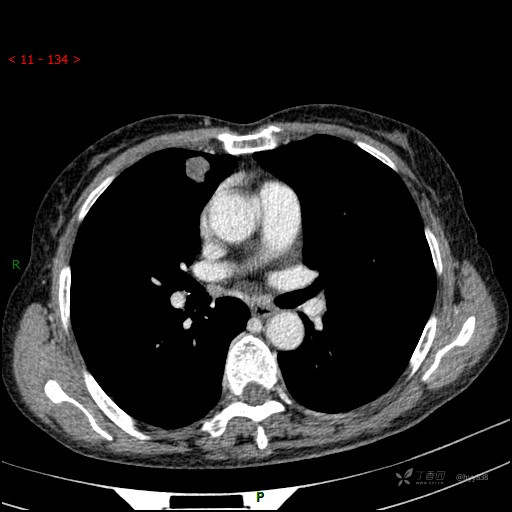

静脉期